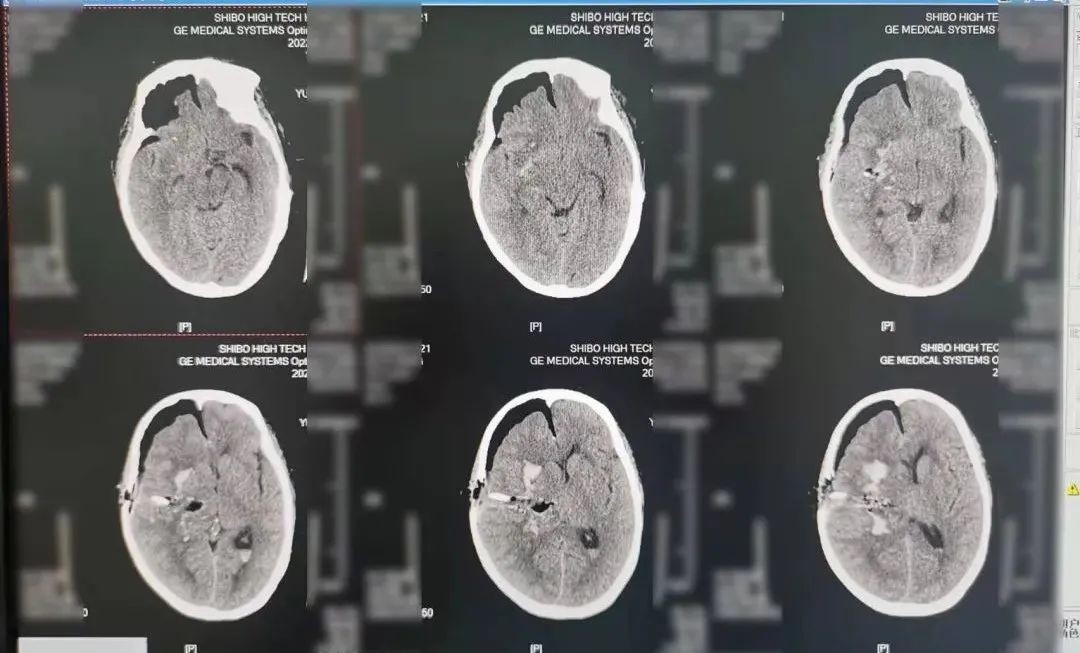

术中,付俊主任凭借丰富经验以及过硬技术,带领团队沉着应战,通过仅2厘米的骨窗将命悬一线的患者从“鬼门关”拉了回来。患者术后复查显示脑内血肿已完全清除,“确实没想到这种大手术能在一个多小时内完成,感谢神经外科团队!”看到复查结果后,患者家属激动不已。

术后复查影像